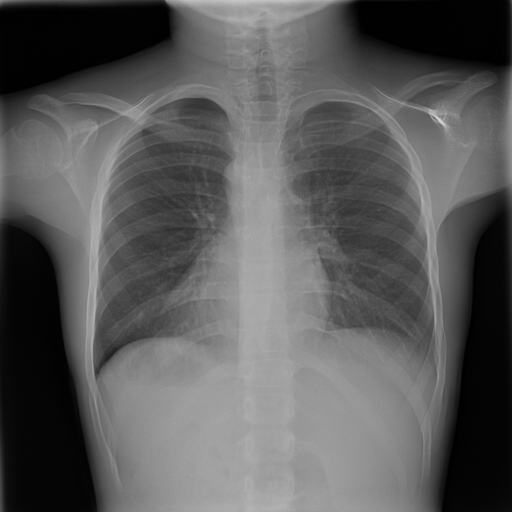

In Fig. 1, we show four ϵitalic-ϵ\epsilon-LDP-processed CXR images of clinical cases obtained with the image domain LDP, which directly imposes the Laplace mechanism on the input image, with different privacy budgets together with the original images. Fig. 2 shows four ϵitalic-ϵ\epsilon-LDP-processed CXR images of clinical cases obtained with DP-GLOW and different privacy budgets together with the original images. In case 1 for DP-GLOW, there is decreased permeability in the bilateral hilar regions. Although this hilar opacity tends to be preserved with a larger privacy budget, the entire image is degraded when the privacy budget becomes 101HWsuperscript101𝐻𝑊10^{1}\cdot H\cdot W. A similar tendency is observed in the images of all the four cases for DP-GLOW; for example, in case 4 with ϵ=101HWitalic-ϵsuperscript101𝐻𝑊\epsilon=10^{1}\cdot H\cdot W, the lung opacity suggesting pneumonia in the right lower lung field is well preserved, while the entire image is degraded.

7.2 Qualitative assessment of LDP-processed CXR images

Here, we assume two possible privacy leakage scenarios. To CXR images, we intentionally add features that can lead to the re-identification of the subject appearing in a CXR image. The first feature is an artificial block marker. The second feature is a rare anatomical abnormality known as situs inversus simulated by flipping a CXR image along the vertical axis. Figs. 3(a) and 3(c) show CXR images with the artificial block marker. Fig. 5(a) shows a flipped CXR image to represent a case of situs inversus. We applied DP-GLOW to these CXR images. In Figs. 3(b) and 3(d), the image domain LDP fails to obfuscate the artificial block marker with a moderate privacy budget. In contrast, in Figs. 4(b) and 4(d), DP-GLOW successfully obfuscated the artificial block marker with the moderate privacy budget. On the other hand, the anatomical shape of the chest and the abnormal opacity (hilar regions in the case 1) are preserved. In Fig. 5(b), we observed that the right edge of the heart does not become obfuscated with the image domain LDP. In contrast, in Fig. 6(b), we observed that the right edge of the heart becomes obfuscated and the heart appears at the center of the thoracic cage with DP-GLOW. However, DP-GLOW with this privacy budget is insufficient to almost completely erase the feature of situs inversus.